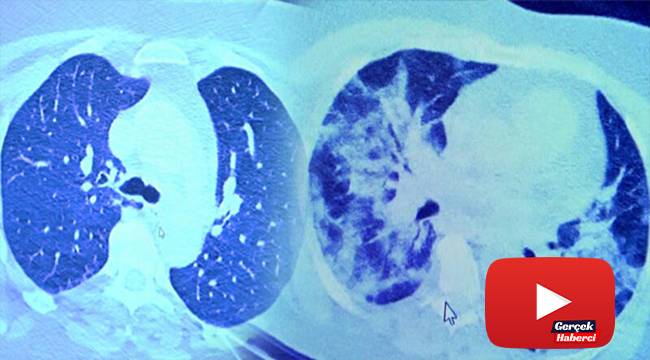

VM Medical Park Samsun Hastanesi’nde görev yapan Göğüs Hastalıkları Kliniği’nden Prof. Dr. Şevket Özkaya da bir hafta ilaç kullanmayan bir pozitif hastanın akciğer tomografisini inceledi. Hasta pozitif haldeyken ilk akciğer tomografisine bakıldı. Tomografide akciğerlerdeki tutulmanın az olduğu gözlemlendi. Akabinde aynı hastanın verilen ilaçları kullanmamış ve 1 hafta boyunca tedaviye uymamış haldeki akciğer tomografisine bakıldı. Sonuç ise ilaç kullanımının önemini ortaya çıkardı. Hastanın akciğer tomografisinde yaygın buzlu camların ve hava yollarının hava yerine ciddi şekilde sıvı ile dolduğu gözlemlendi.

Akciğer tomografisinde oluşan değişim ile ilgili bilgi veren Prof. Dr. Şevket Özkaya, "Ekranda 55 yaşında bir kadın hastamızın filmini görüyorsunuz. Bu kadın hastamız acil servisimize ateş şikâyetiyle geldi ve korona virüsünden şüphe ettik. Testini yaptığımızda ise testin sonucu pozitif geldi. Tomografi çektiğimiz zaman akciğerlerinde henüz ciddi bir tutulum görünmezken hastamız 55 yaşında olduğu için her an ilerleyebilir korkusuyla Sağlık Bakanlığımızın önerdiği ilaçları ve reçeteyi hastanemizden kendisine verdik. Hasta kendini evde karantinaya aldı fakat sonradan öğrendik ki tereddüt ettiği için ilaçlarını kullanmayarak kendini evde tedavisiz bırakmış. Yaklaşık bir hafta sonra aynı hasta acil servisimize bu sefer solunum yetmezliği şikâyetiyle geldi. Solunum yetmezliği gelişince hastanın akciğer tomografisinde ‘buzlu cam’ dediğimiz ve daha ileri konsolide alanların oluştuğunu gördük. Yaygın akciğer harabiyeti dediğimiz bir tablo oluşmuştu. Bu durumda hastada solunum yetmezliği olduğu için yoğun bakıma almak zorunda kaldık" dedi.